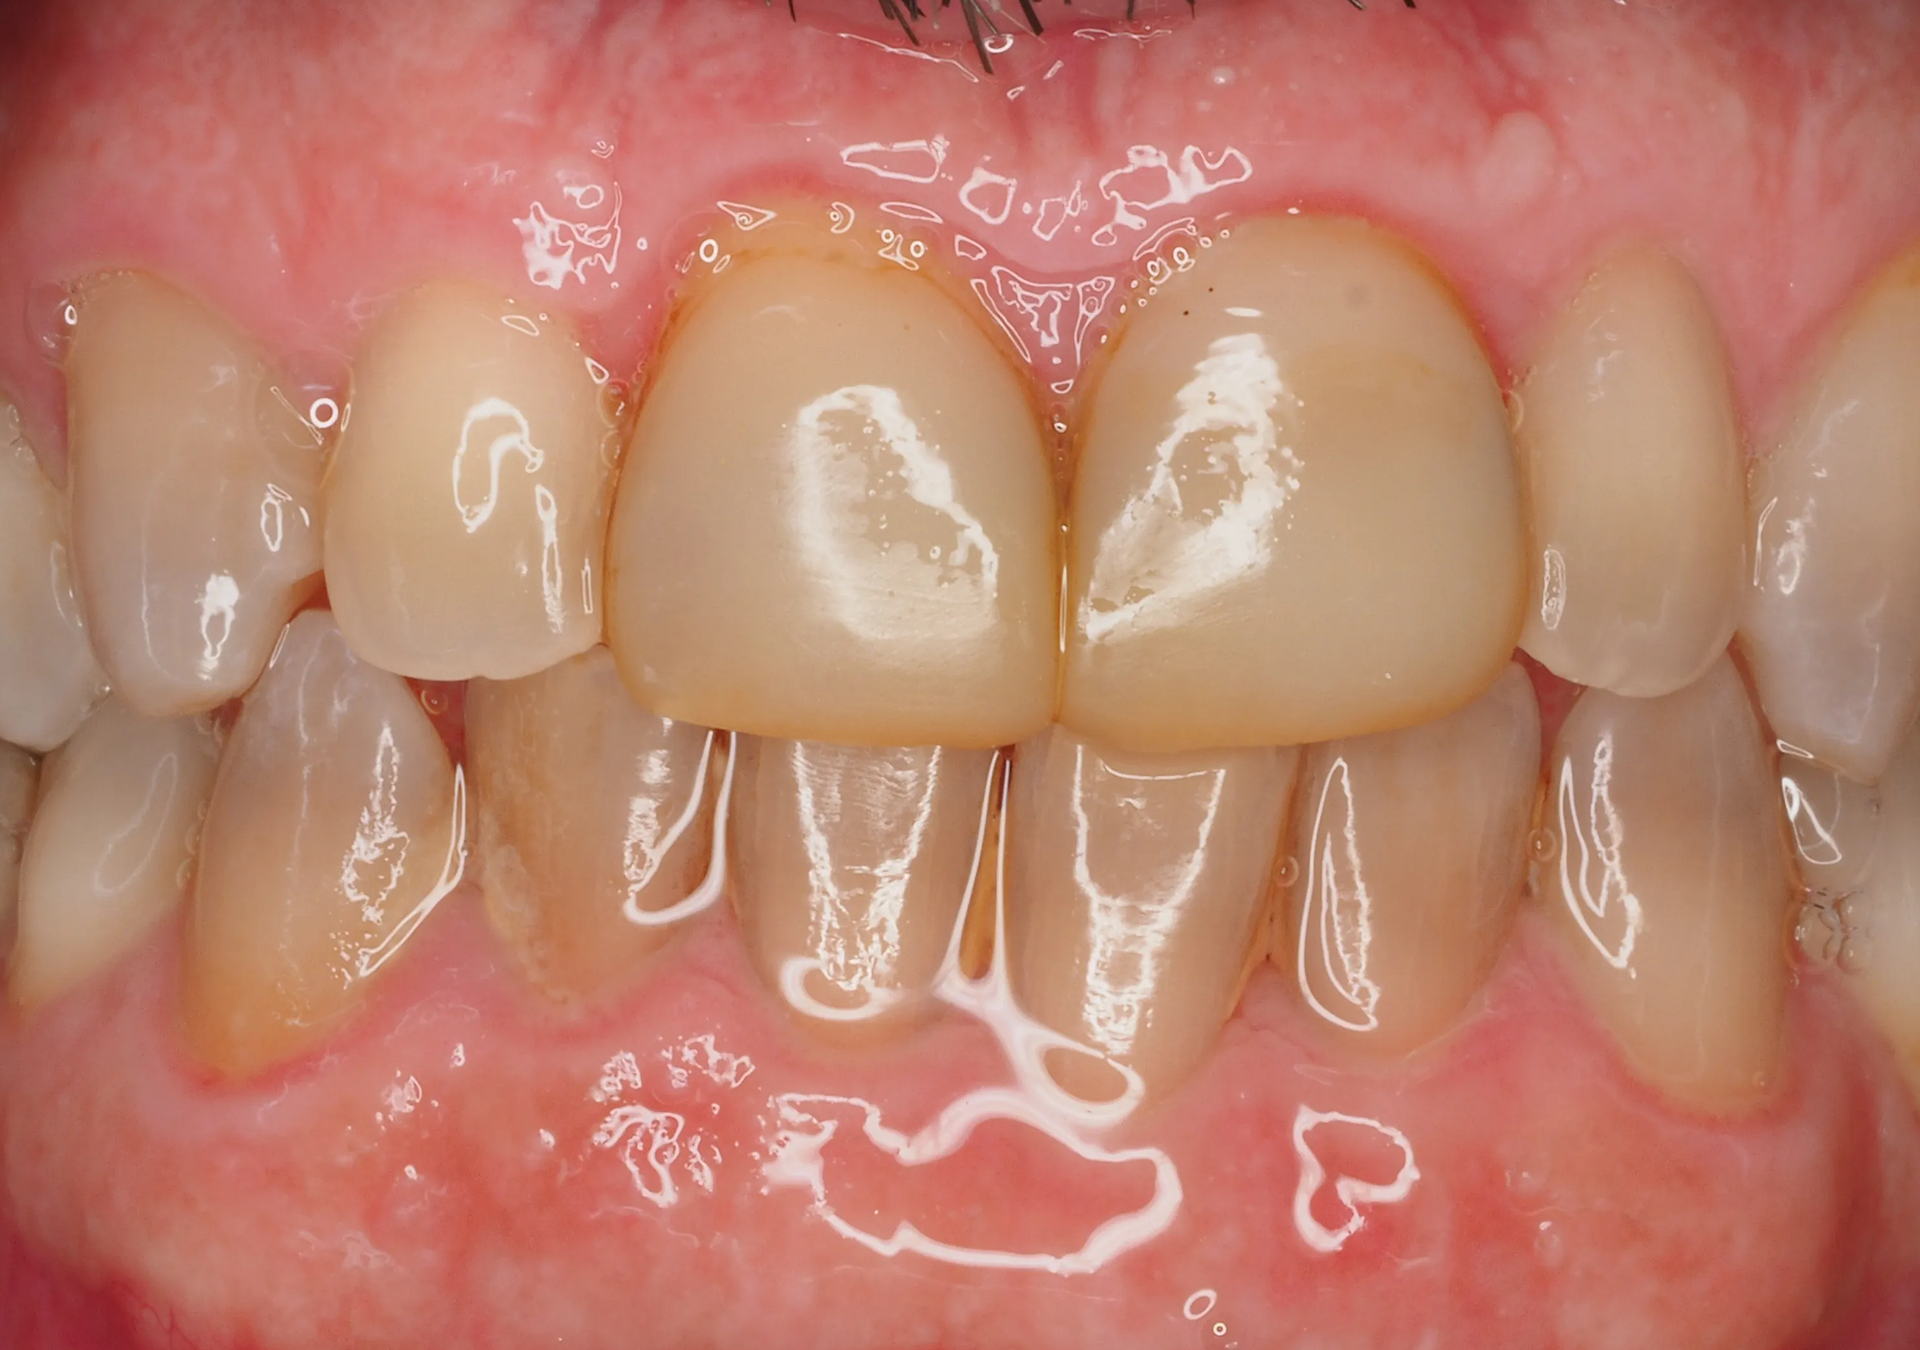

- 25 años de experiencia en restauraciones de resina composite tanto en sectores anteriores como posteriores.

- Resultados estéticos comparables a la cerámica, de larga durabilidad.